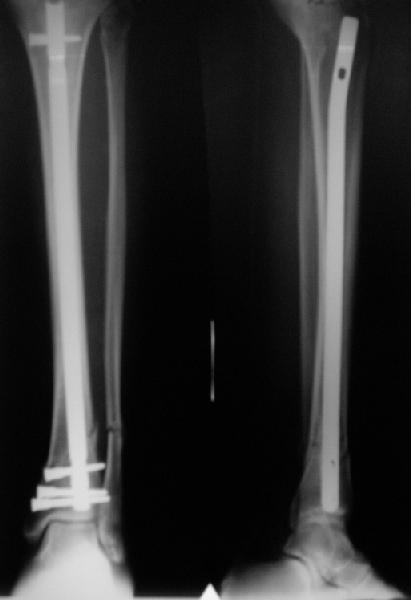

A typical case is attached, also an image with intra-op reduction obtained by a small wire distractor, in the moment of insertion a Poller wire in AP direction. Fixation by a SIGN nail. Despite the fibula was not fixed healing was obtained with the unchanged alignment.

Отправитель: Alexander Chelnokov 21 Май 2006, 23:21

I am just trying to illustrate that prevention of 1)tibial valgus and 2)loss of reduction can be provided without fibular plating. Small changes of conventional nailing techniques allow to maintain reduction of the tibia reliably without adjunctive fibular stabilization.

In delayed cases acute length restoration performed only in the tibia may leave the fibula shortened thus change the mortise. So it is reasonable to restore length of both bones simultaneously by distractor and fix the fibula not with open reduction and plating but just by a single perQ screw. Example attached.

As i mentioned a small wire distractor was used. In common upper fractures it is enough to insert 2 frontal wires to the proximal fragment - one in the upper posterior aspect of the tibia and the second anteriorly and a bit more distally. The technique allows to avoid such known tricks like more lateral entry point, semi-extended knee, extended approach, using of bone clamps, plating with monocortical screws etc.

In this particlar case 4 frontal wires were inserted in anterior and posterior aspects at both sides of proximal fracture, and fixed to a single half ring with some bend to provide compression with wire tension. Image attached.

На одной опоре, расположенной чуть дистальнее обычного, были закреплены 4 спицы, проведенные во фронтальной плоскости, по 2 в передней и задней части смежных фрагментов. Закреплены так, чтобы при их натяжении создалась компрессия. Картинка в приложении.